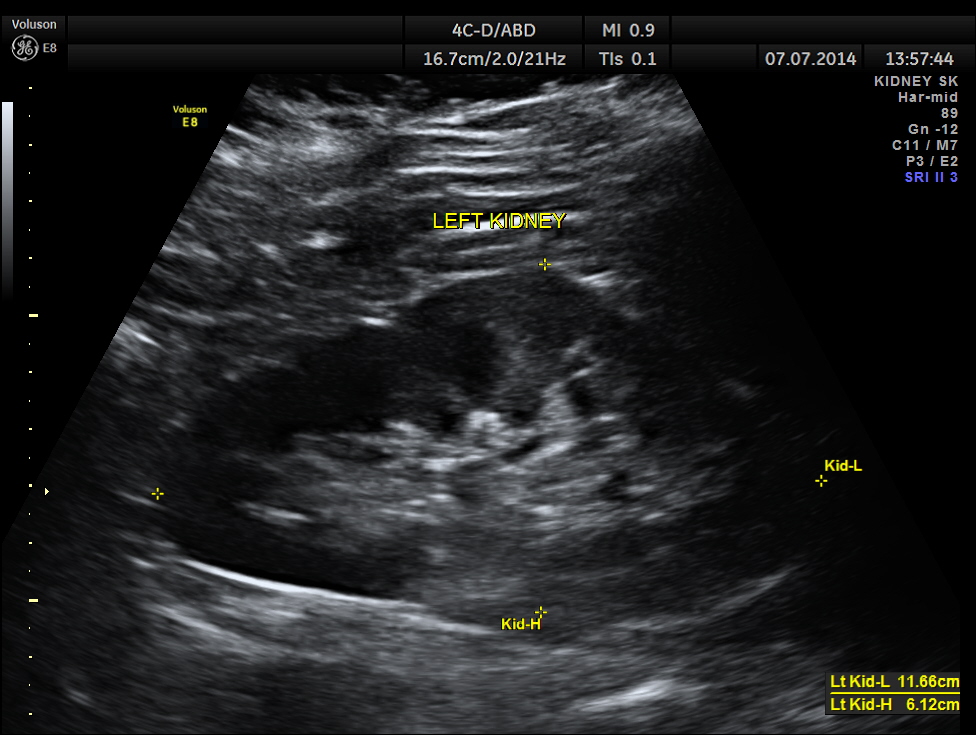

The left kidney appears to be normal.